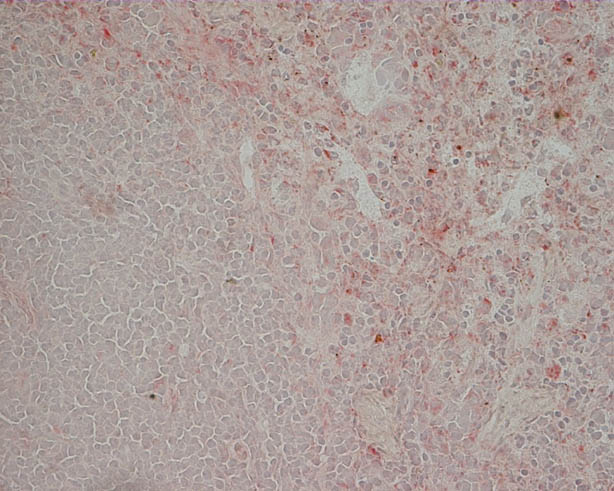

Bottom: Liver of a mouse, 2 days after injection with clodronate-liposomes. Kupffer cells have been depleted